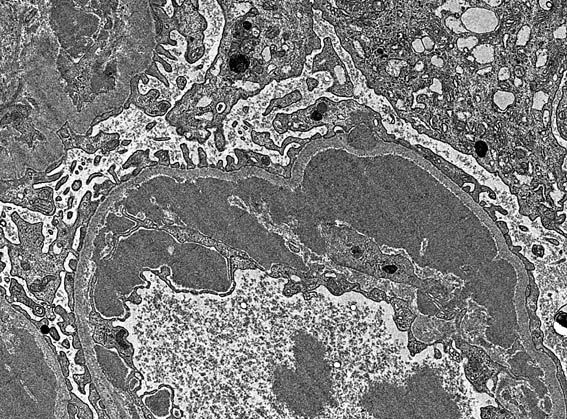

Figura 5. ME, aumento original, X3.000.